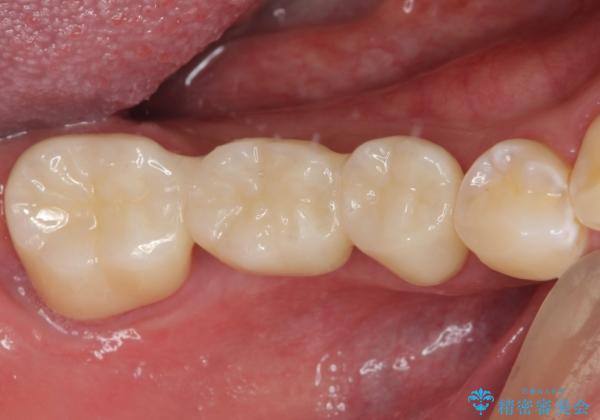

- 以前他院にて、保険診療で治療した金属のブリッジをやり替え希望の患者様です。

奥歯であっても、大きく笑うと金属色が目立ちます。

金属ブリッジを除去し、虫歯を完全に除去し、形を整え、

精度の高いシリコーン材料にて型どりをしました。

精度の高いブリッジなので、しみるなどの症状もなく経過も良好です。